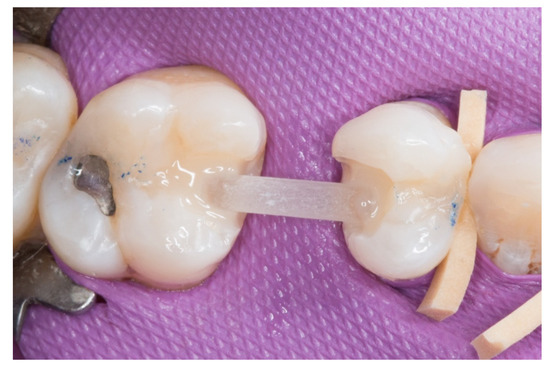

The transverse structure of the future fiber-reinforced composite bridge (FRCB).

Figure 4.

The horizontal fiberglass pin bonding to the adjacent teeth.

Figure 5.

3. The next step consisted of the horizontal fiberglass pin (Rebilda® Post GT, VOCO GmbH, Cuxhaven, Germany) bonding to the adjacent teeth. Firstly, when the isolation of the operative field with the rubber dam was made, the fiberglass pin was adjusted to size and silanization according to the instructions by the manufacturer. Later, the inlay cavities were etched with Ultra-etch® (Ultradent Products Inc, South Jordan, UT, USA) for 20 s, rinsed for 10 s and dried for 10 s. The etched surfaces were covered with a layer of a universal adhesive resin (Prime & Bond® NT, Dentsply Sirona Inc., York, PA, USA), thinned using a brush, and cured for 20 s with a light- polymerizing unit. A flowable resin (Tetric Evo flow®, Ivoclar Vivadent AG, Schaanwald, Liechtenstein) was used to cover the inlay cavities (inlays retainers) and the fiberglass pin to shape the transverse structure of the future bridge (Figure 3 and Figure 4).

4. Afterwards, the pontic core was reinforced with a vertical pin fiberglass structure, which was followed by the same adhesion process mentioned above, obtaining a “T” shape (Figure 5).